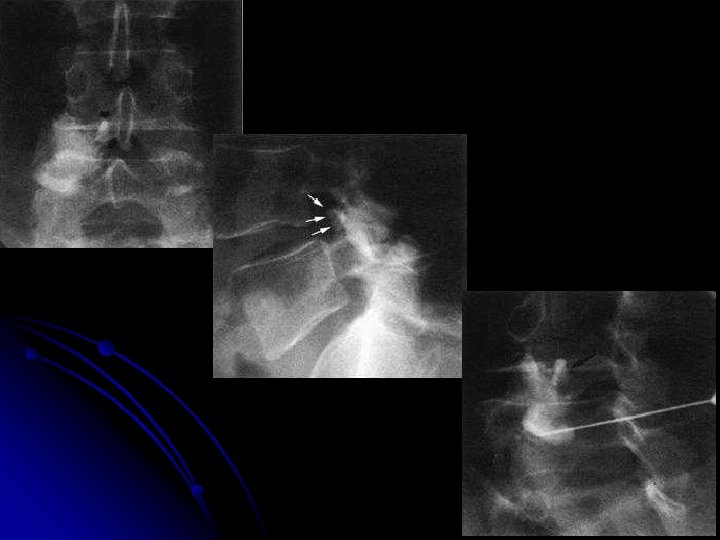

ARTHROGRAPHIE INTERAPOPHYSAIRE POSTERIEURE